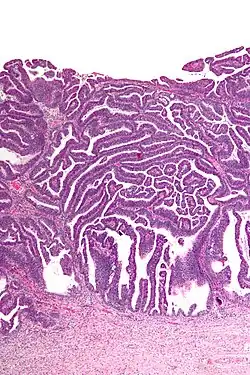

| Micrograph of a villoglandular adenocarcinoma the cervix. H&E stain. | |

The name of the lesion describes it microscopic appearance. It has nipple-like structures with fibrovascular cores (papillae) that are long in relation to their width (villus-like), which are covered with a glandular pseudostratified columnar epithelium.